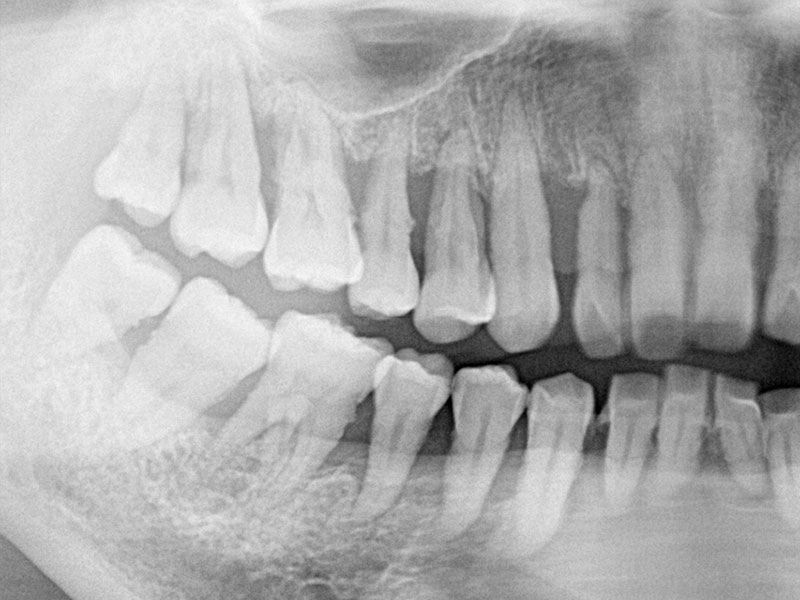

45歳の時